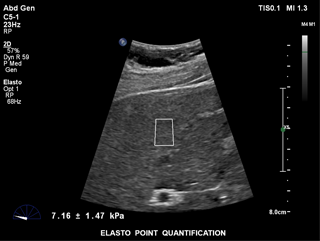

ElastPQは、事前に置いたROIで肝組織の硬さの値を取得することができる、使いやすい手法です。リアルタイムイメージングをガイドとし、関心領域にROIを置くと、数秒で組織の硬さデータ(AVG、MEAN、IQRなど)を取得して表示します。複数のサンプルを記録し、測定結果をレポート表示します。